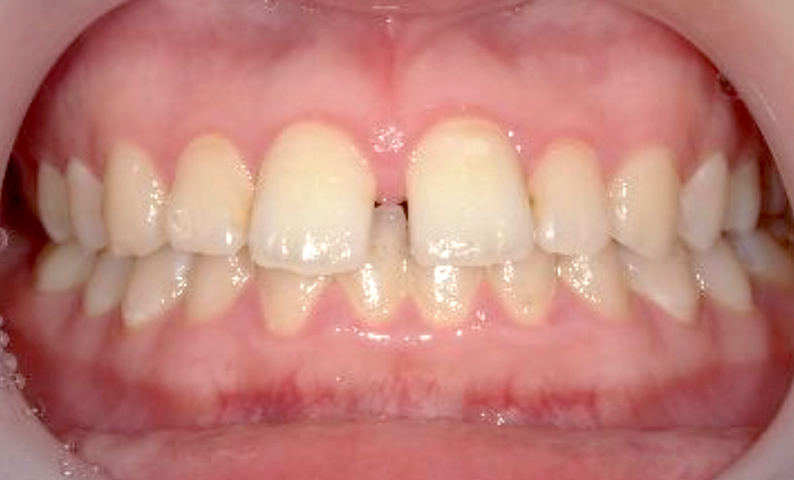

| 治療前 | 治療後 |

|---|---|

|